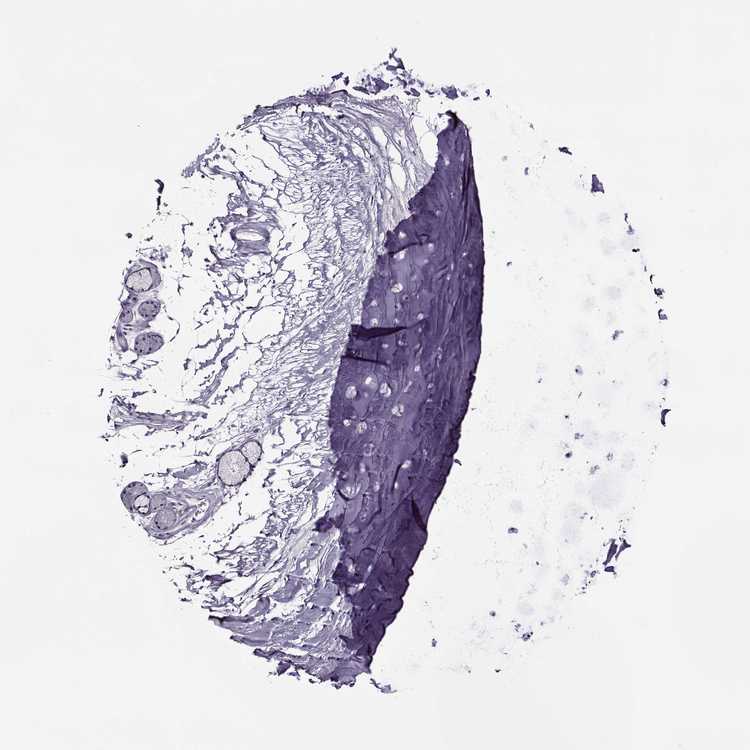

ADIPOSE TISSUE - Antibody stainingi

Antibody staining in the annotated cell types in the current human tissue is reported as not detected, low, medium, or high, based on conventional immunohistochemistry profiling in selected tissues. This score is based on the combination of the staining intensity and fraction of stained cells.

Each image is clickable and will lead to virtual microscopy that enables deeper exploration of all samples and also displays staining intensity scores, fraction scores and subcellular localization as well as patient and tissue information for each sample.

Antibody HPA001193Antibody HPA002820

Adipocytes Not detectedNot detected